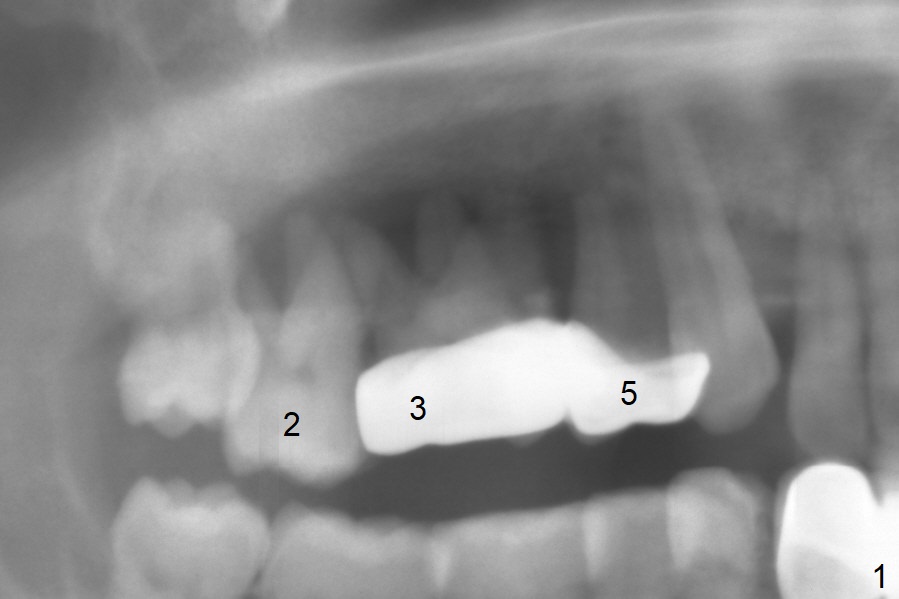

A 45-year-old man will return for #2, 3 and 5 extraction and implants (Fig.1,2). Take PAs for and Reline #7,9,11 provisional crowns and fabricate #11-13 temporary FPD if #15 implant is still unstable (5 months postop). Establish normal occlusal contact.

Extract #2 or remove #3-5 FPD first whichever is looser. Use the other as reference guide. Place Osteogen plug in the palatal socket of #2 ad 3 (Fig.3,4 yellow box) and allograft around the implants (red circles).